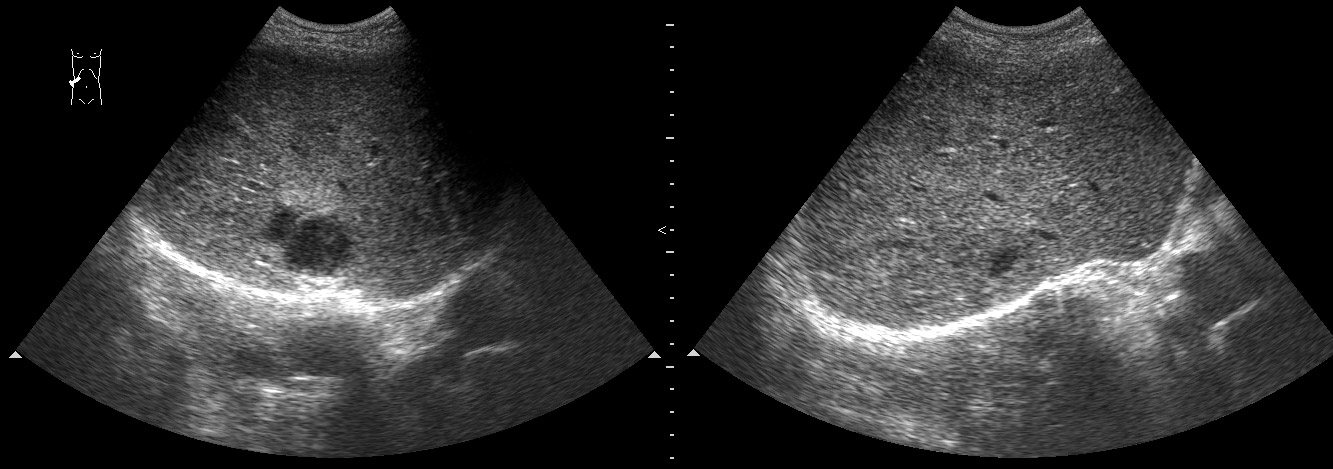

Маленький абсцесс печени до и на фоне 1 недели АБ-терапии

Те, которые не можем задренировать - проводим АБ-терапию.

abscess-one_week_treatment.jpg

А какие ограничения для дренирования были в данном случае?

Плохая доступность. Был расположен очень высоко и был небольших размеров.

Решено было вести консервативно.